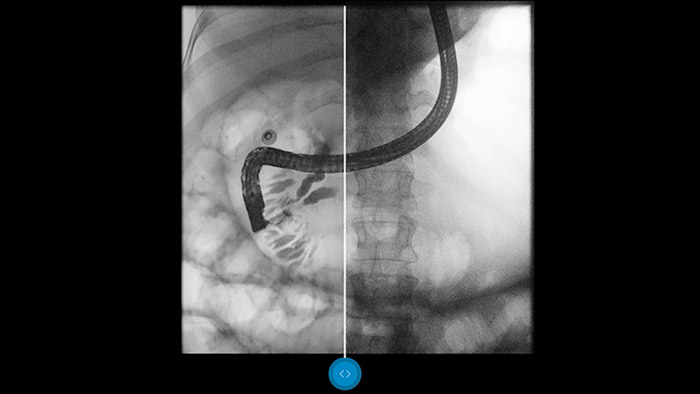

Porównaj bezpośrednio z obrazami po konwencjonalnym przetwarzaniu i zobacz korzyści dla siebie.

Zastosowanie oprogramowania do obróbki obrazów Dynamic UNIQUE powoduje ujednolicenie poziomu kontrastu, wzmocnienie mało widocznych szczegółów i zapewnia niezmienną jakość obrazów, co pozwala jasno określić różnicę między kośćmi a tkanką miękką.

Dynamic UNIQUE delivers excellent detail with overall contrast harmonization – even in challenging viewing conditions. Each and every frame is fully processed in real-time and optimally enhanced. There are no enhancement artifacts. There is no image clipping. So you are less likely to miss important details*.